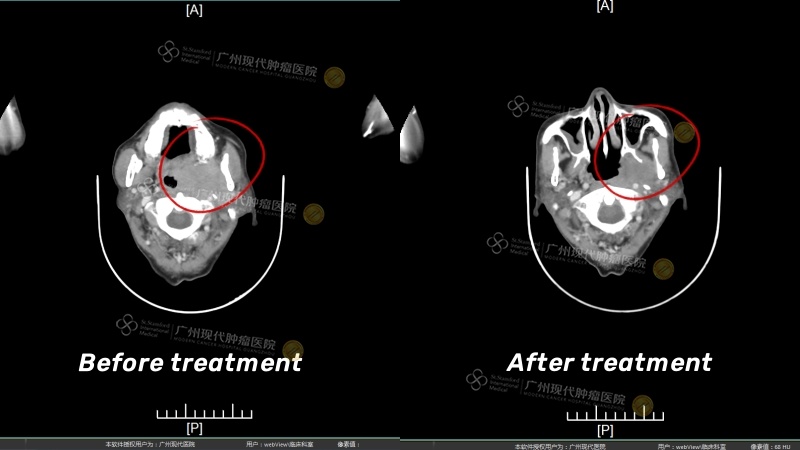

Before treatment, the tumor size of about 6.1cm x 4.0cm completely blocked the nasopharynx, and the tumor was significantly reduced after treatment

Before treatment, my mouth felt thirsty every day, my hearing was unstable, my nasal cavity felt abnormal and it was difficult to swallow, my tongue was numb, my speech was unclear, and I often had low-grade fevers and nosebleeds. But after one course of treatment, all my symptoms disappeared significantly in just a few days: nosebleeds, slight fever, tongue abnormalities, nasal cavity abnormalities and other symptoms disappeared! Hearing is also normal! After three minimally invasive treatments, not only was there no pain or fainting caused by systemic chemotherapy, but the egg-sized tumor had almost disappeared!